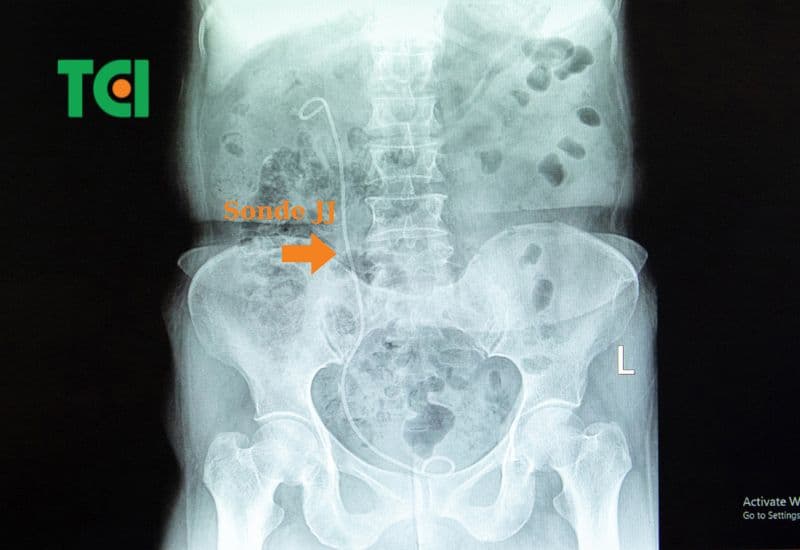

Rút ống thông niệu quản/ sonde JJ có đau không?

Thực hiện rút ống thông JJ niệu quản tại TCI sau tán sỏi công nghệ cao